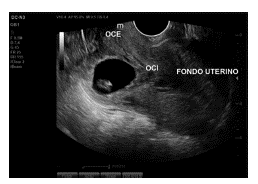

Debido a la localización del saco gestacional y los posibles riesgos secundarios, como son la ruptura uterina, hemorragia severa, la posibilidad de requerir histerectomía secundaria a esta implantación y el riesgo de falla terapéutica con MTX debido a niveles iniciales de BhCG y embriocardia presente, se plantea manejo quirúrgico, sin embargo, con deseo de fertilidad, a pesar de explicar posibles complicaciones, se decide en conjunto intentar manejo farmacológico con MTX, recibiendo una dosis de 80 mg/sm2 el primer y cuarto día. Se realiza seguimiento de la hormona gonadotropina coriónica humana (BhCG), con aumento en los niveles de la hormona, de 37945,60 mUI/ml y en el control eco-gráfico se evidencia persistencia de embriocardia, por lo cual se decide administrar una tercera dosis de MTX. Posterior a esto, se realiza nuevo control ecográfico en el cual se encuentra saco gestacional de 25 mm, localizado en istmo vs. cicatriz uterina previa con presencia de embrión con longitud cráneo caudal de 12.2 mm para un embarazo de 7,3 semanas con actividad cardiaca presente en 139 lpm, sin evidencia de líquido libre (Figuras 2 y 3).